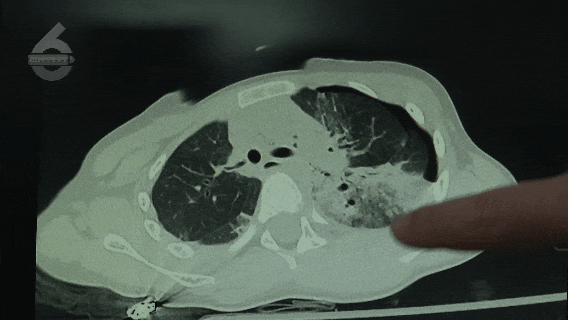

昆明市儿童医院SICU医生 谢超:“当时她摔下来的时候被树隔挡了一下,所以没有造成严重的颅脑损伤,只是脑的挫裂伤。但当时比较严重,威胁到她生命的是全身多发的损伤,包括严重的肺挫伤、出血,然后血气胸、膈肌损伤、腹部的胃破裂、脾破裂,还包括四肢有骨折,是一个严重休克的状态。”

昆明市儿童医院SICU医生 谢超:“这个孩子的伤情最关键的点就是,在高坠的时候没有直接摔到头,她的第一下着力的点应该不是在头部。虽然她有脑挫裂伤,但是不严重,如果这样的病人从23楼摔下直接摔到头,或者没有树的隔挡直接摔到其他地方的话,可能也就回天无力了。”